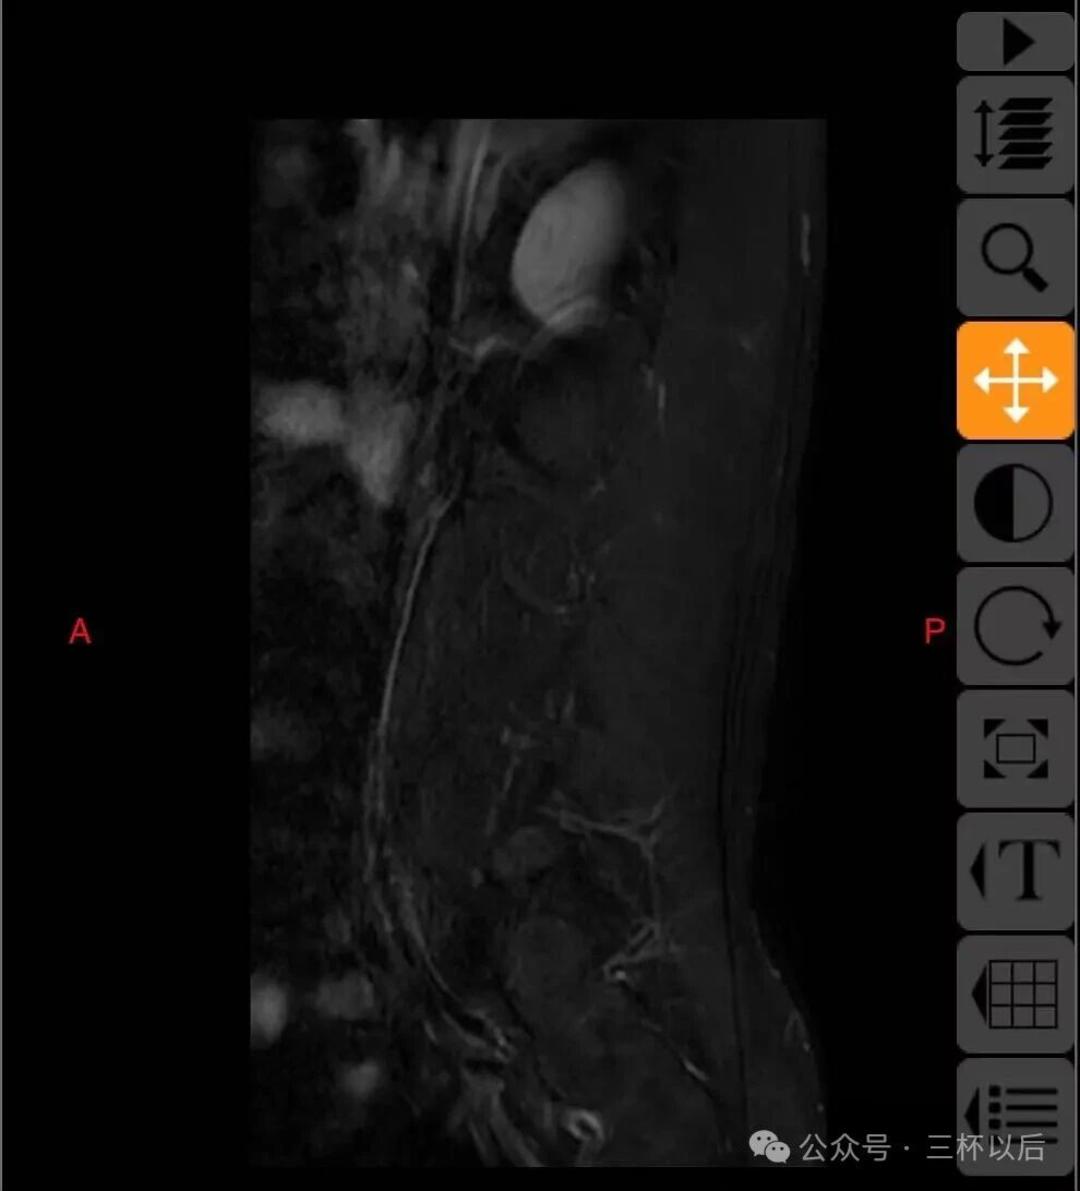

顺便贴一下拍的片子,如果有懂行的欢迎给我建议,我听劝的。真真希望能恢复如初,现在每天都能感受到疼痛,用了各种办法也不管用。